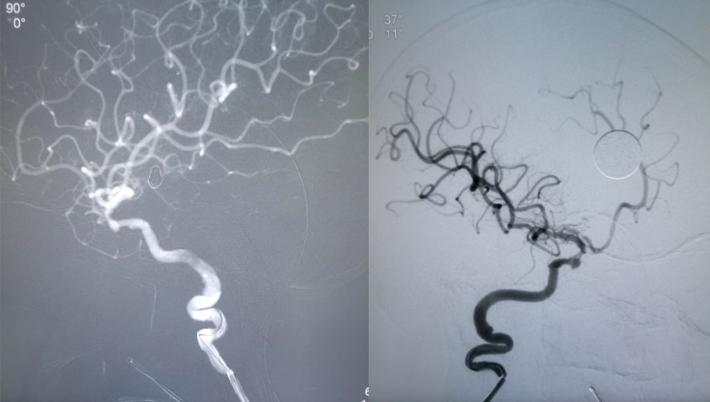

对侧造影评估,前交通开放,左侧大脑前动脉经开放良好的前交通动脉向右侧大脑前动脉A2段各分支血管供血良好,结束手术

✔Enterprise支架释放后,右侧大脑前动脉A1段未显影,考虑可能为支架打开后,对病变段血管的修复及一定血流导向作用,大脑中动脉前向血流增加,而原本纤细的左侧大脑前动脉A1段血流减少,对侧大脑前动脉通过前交通动脉向左侧大脑前动脉A2段主流供血,由于血流对冲作用至左侧大脑前动脉A1段不显影。后对侧评估前交通开放,对侧代偿良好,结束手术。术后患者亦未再出现新的神经系统体征,肢体活动及语言功能恢复良好,1周后头颅CT未见新发梗死灶。